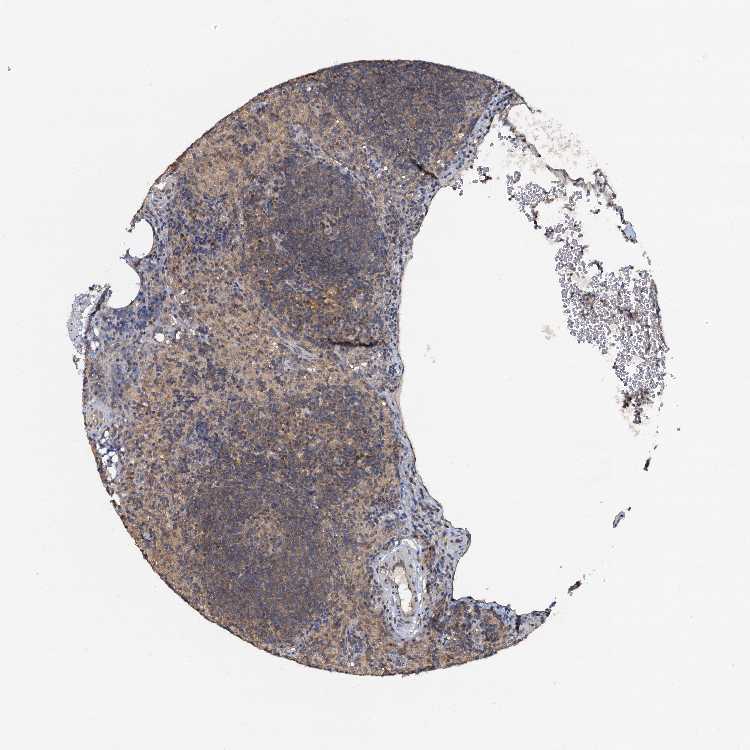

TISSUE PRIMARY DATA LYMPH NODE Show tissue menu

Lymph node

LYMPH NODE - Expression summary

LYMPH NODE - Antibody stainingi

Antibody staining in the annotated cell types in the current human tissue is reported as not detected, low, medium, or high, based on conventional immunohistochemistry profiling in selected tissues. This score is based on the combination of the staining intensity and fraction of stained cells.

Each image is clickable and will lead to virtual microscopy that enables deeper exploration of all samples and also displays staining intensity scores, fraction scores and subcellular localization as well as patient and tissue information for each sample.

Antibody HPA038672Antibody HPA038673Antibody CAB034319

Germinal center cells LowLowLow

Non-germinal center cells LowMediumMedium